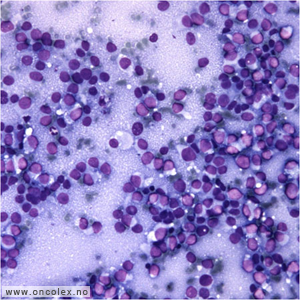

Histologisk ses små runde celler med sparsomt cytoplasma. Cellene er glykogenholdige, noe som kan påvises med PAS histokjemisk. Enkelte tilfeller kan vise mer pleomorfe celler. Det er ingen matrixproduksjon. Rosetter kan påvises og er relatert til neuroektodermal differensiering. Tumor er per definisjon høygradig malign og noen gradering er ikke meningsfull.

Histologisk bilde av Ewings sarkom. |

Cytologisk bilde av Ewings sarkom. |